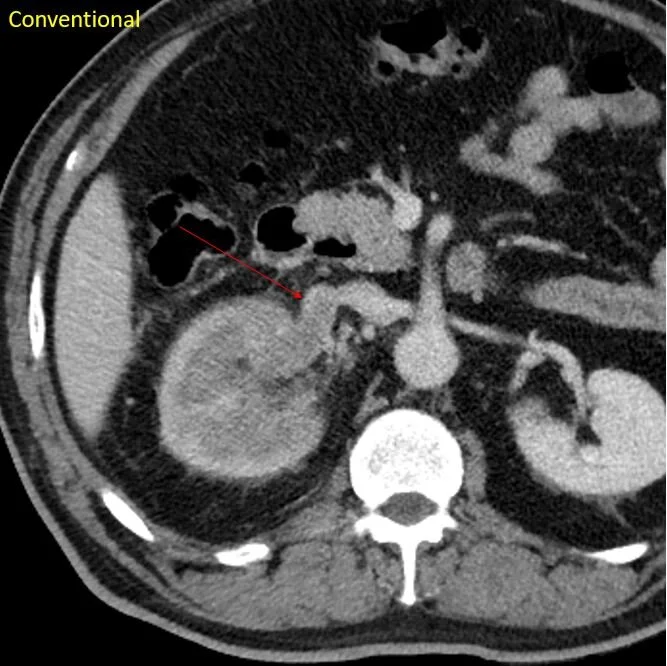

CT a couple of years later. Intensely enhancing subcarinal nodule.